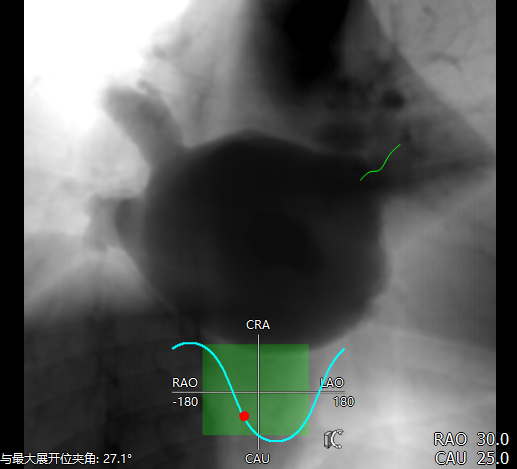

采用CT模拟最佳左心耳封堵工作体位,发现在RAO30 CAU25时左心耳展开较常规体位更好。

RAO30 CAU25

RAO30° CAU25°造影,左心耳形态充分暴露,可以观察到心耳属于反鸡翅形状。内部梳状肌较发达,深度较浅。